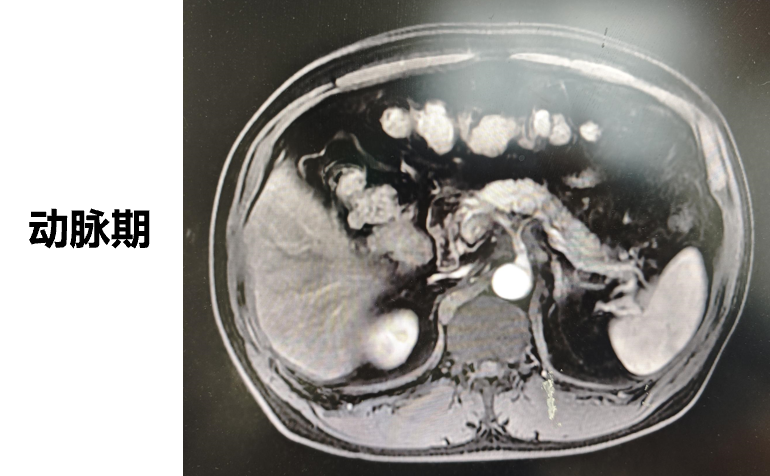

◈ 2022-7-19腹部MR增强扫描:提示T2WI及DWI胰腺体尾部信号稍高并胰管局限性稍扩张,肠系膜上动脉、腹腔干近段局部管壁增厚,需鉴别免疫相关性疾病累及或其他。

2022-7-19 上腹部MR增强扫描